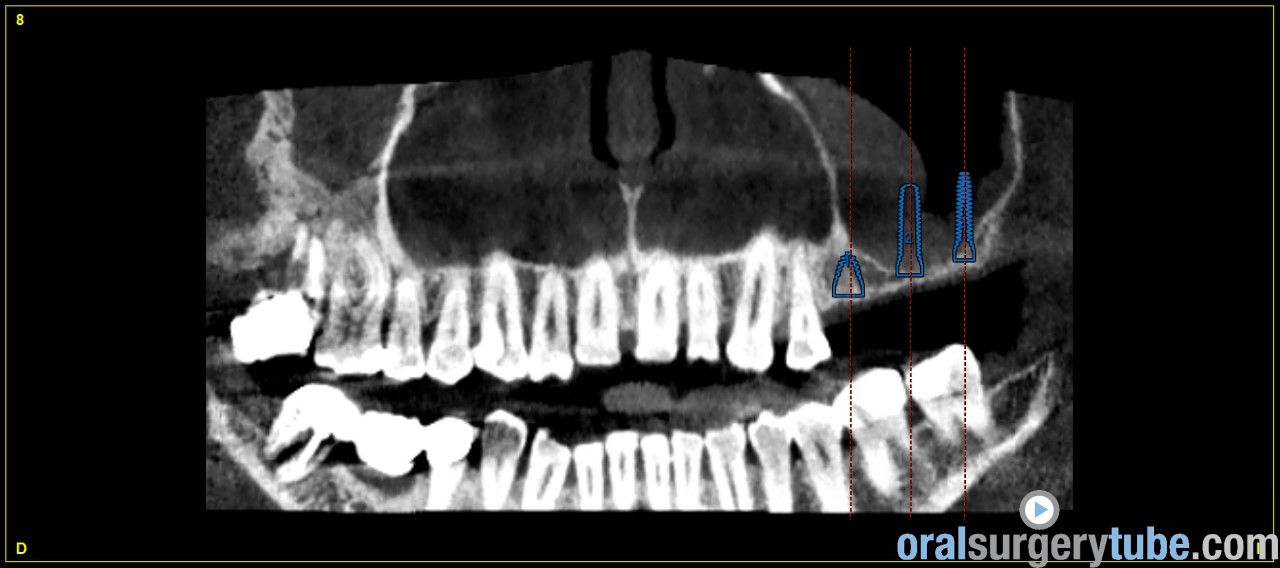

Engrosamiento mucoso

Estimados compañeros, me gustaria saber como abordaríais el seno izquierdo el cual como veis presenta engrosamiento mucoso. Haríais tratamiento previo? Gracias de antemano

Jesús me gustaría poder ver una vista panorámica, yo cada vez más tiro de pterigoideos, muchas veces elevando la mb de snneider y colocando el pterigoideo y la elevación sinusal. Me llama la atención el engrosamiento unitaleral tb del cornete.uhmmmm prueba a darle un antihistamício, tipo loratadina, ebastina (R), ebastel(R) juraría que de 20 mgr, aunque lo habitual es que si es alérgico, fuese bilateral. Pero,..... Gracias por tus comentarios, y presencia.

Que opináis de dar un corticoide vía oral? Como la dexametasona?. Por cierto repetí el tac después de hacer la elevación derecha y de dar antibiótico y la verdad que el engrosamiento del sebo izquierdo a cambiado más bien poco por no decir que incluso se ha engrosado un poco más, pero eso sí, el paciente no refiere haber tenido en toda su vida síntomas de sinusitis ni alergia, imagino que la causa es la desviación que se ve del tabique hacia la izquierda y la concha bullosa del cornete medio, de verdad no se q hacer, si abordar el seno así ( ya que el paciente no tiene síntomas ) o derivarlo a un otorrino.Tampoco me parece exagerado el engrosamiento, qué opináis?

Hola a todos. Al hilo de este post que he visto, os presento un caso que me ha llegado hace poco a la consulta. Os envío imagenes. Se aprecia engrosamiento de la membrana del seno maxilar izdo. Pensaba darle Trigon Depot 10 días antes de la cirugía y luego valorar. Como lo veis? Muchas gracias.